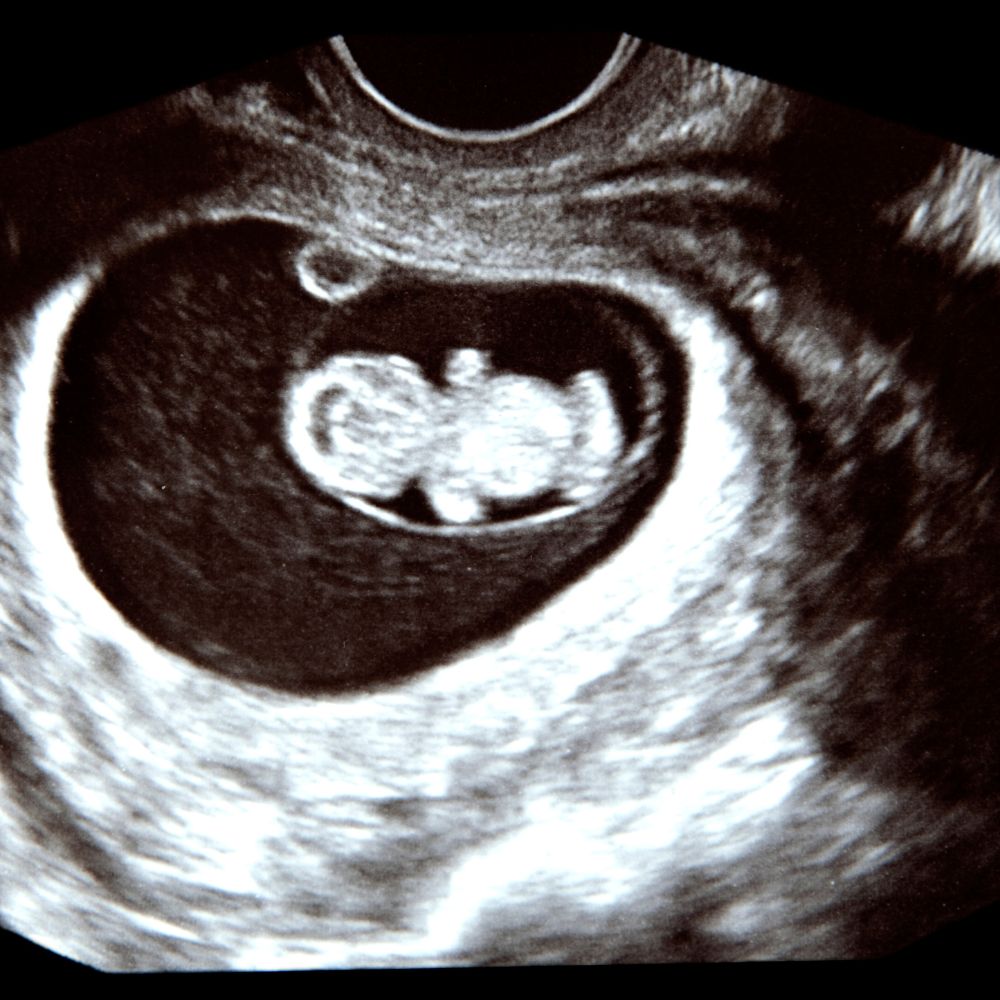

4-2. 병원 검진 시기

테스트기로 양성 반응이 나왔다면, 산부인과를 방문하여 정확한 진단을 받는 것이 좋습니다. 보통 마지막 생리 시작일로부터 5-6주가 지나면 초음파로 임신낭을 확인할 수 있고, 6-7주가 되면 태아의 심장 박동을 확인할 수 있습니다.